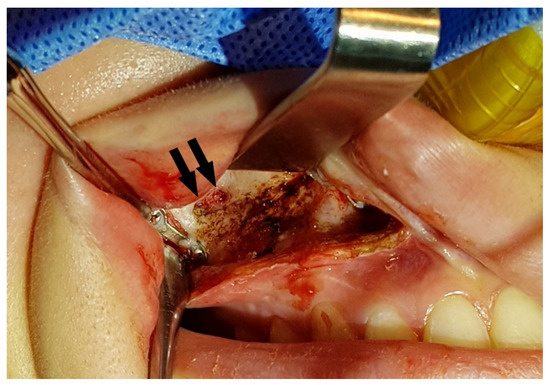

During the Le Fort I osteotomy, autogenous block bones were grafted at the bony gap of the anterior maxilla for postoperative stability of the maxilla and for achieving a more efficient drainage of the maxillary sinus by minimizing the communicating spaces (Figure 6).

Figure 6.

Autogenous block bone (arrows) was grafted at the bony gap of maxillary sinus wall for a more efficient drainage of maxillary sinus.